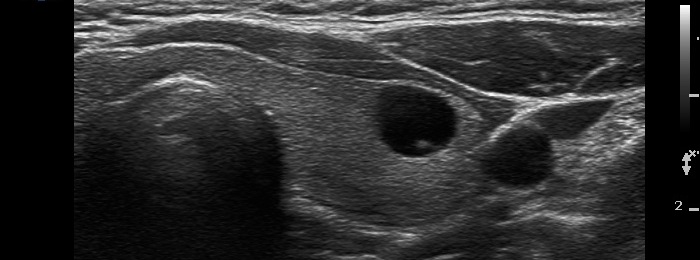

After aspiration of 2 mL cystic fluid |

It became more evident after removal of the cystic fluid that the figures are comet-tail artifacts.